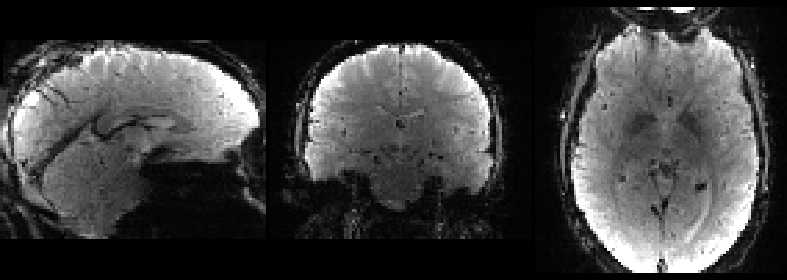

View the outputs to make sure that these steps worked. The results don’t need to be perfect, just reasonably good:

fsleyes structural -cm blue structural_fov structural_fov_brain -cm hot &

You are looking at three images here - the blue one in the background (if you can see it) is the raw T1 image, the grey one is the T1 image after the FOV has been tightened with robustfov, and the red-yellow image is the T1 image after non-brain voxels have been zeroed out by bet.